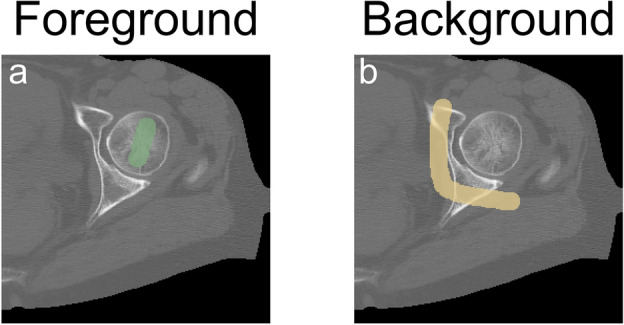

Figure 4.

Example of the labelling performed by the operator. Left: in green, labels for the foreground voxels. Right: in yellow, labels for the background. Limited and not necessarily precise labelling was sufficient to initialise the graph-cut.